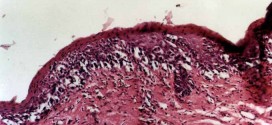

Leer MásLUPIA

La lupia. Quiste sebáceo (lobanillo). Por retención en una glándula sebácea visible bajo la piel. Localizado en la nuca, la espalda y sobre todo en el cuero cabelludo. Existe otro tipo de quiste folicular, denominado quiste tricolémico (vulgarmente llamados lobanillos), también muy frecuente. Se diferencia del quiste epidermoide en que se origina en una zona diferente de la pared del …